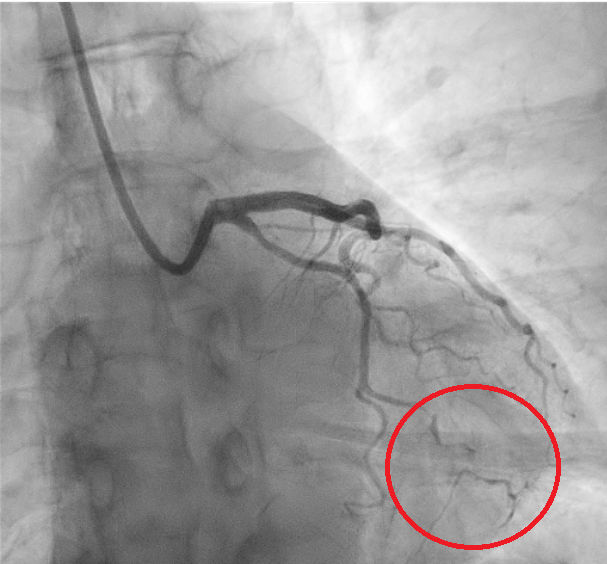

We report the case of a 61-year-old woman presenting with chest pain radiating to the left arm. EKG showed inferolateral repolarization abnormalities. Laboratory revealed mild elevation in troponin (0.76). Transthoracic echocardiography demonstrated mildly reduced systolic function with posterolateral wall akinesia (ejection fraction 48%). The patient was referred for coronary angiography showing no significant stenoses; however, a focal narrowing of the proximal circumflex artery (LCX) was observed, consistent with type 3 spontaneous coronary artery dissection (SCAD) according to the Yip–Saw classification (Fig. 1). Given the risk of iatrogenic propagation of the dissection and recommendations to minimize coronary instrumentation in SCAD, intracoronary imaging was avoided, and we performed instead coronary computed tomography angiography (CCTA) demonstrating mild stenosis of the LCX with mural hyperdensity, consistent with an intramural hematoma (Fig. 2). On day four, the patient experienced angina similar to the initial episode, with ECG changes and an increase in troponin (1.2). Repeat coronary angiography demonstrated progression of the dissection from the LCX to the distal segment of the first obtuse marginal branch, corresponding to evolution toward type IIb SCAD (Fig. 3). Given the limited myocardial territory at risk and the absence of ongoing symptoms, conservative management was continued. Patient was discharged on day ten on a beta-blocker and aspirin.with a planned follow-up CCTA at six months. This case highlights that in SCAD, particularly type 3 and proximal lesions, a conservative approach is often the safest strategy, with non-invasive imaging playing a key role in diagnosis, follow-up, and therapeutic guidance.